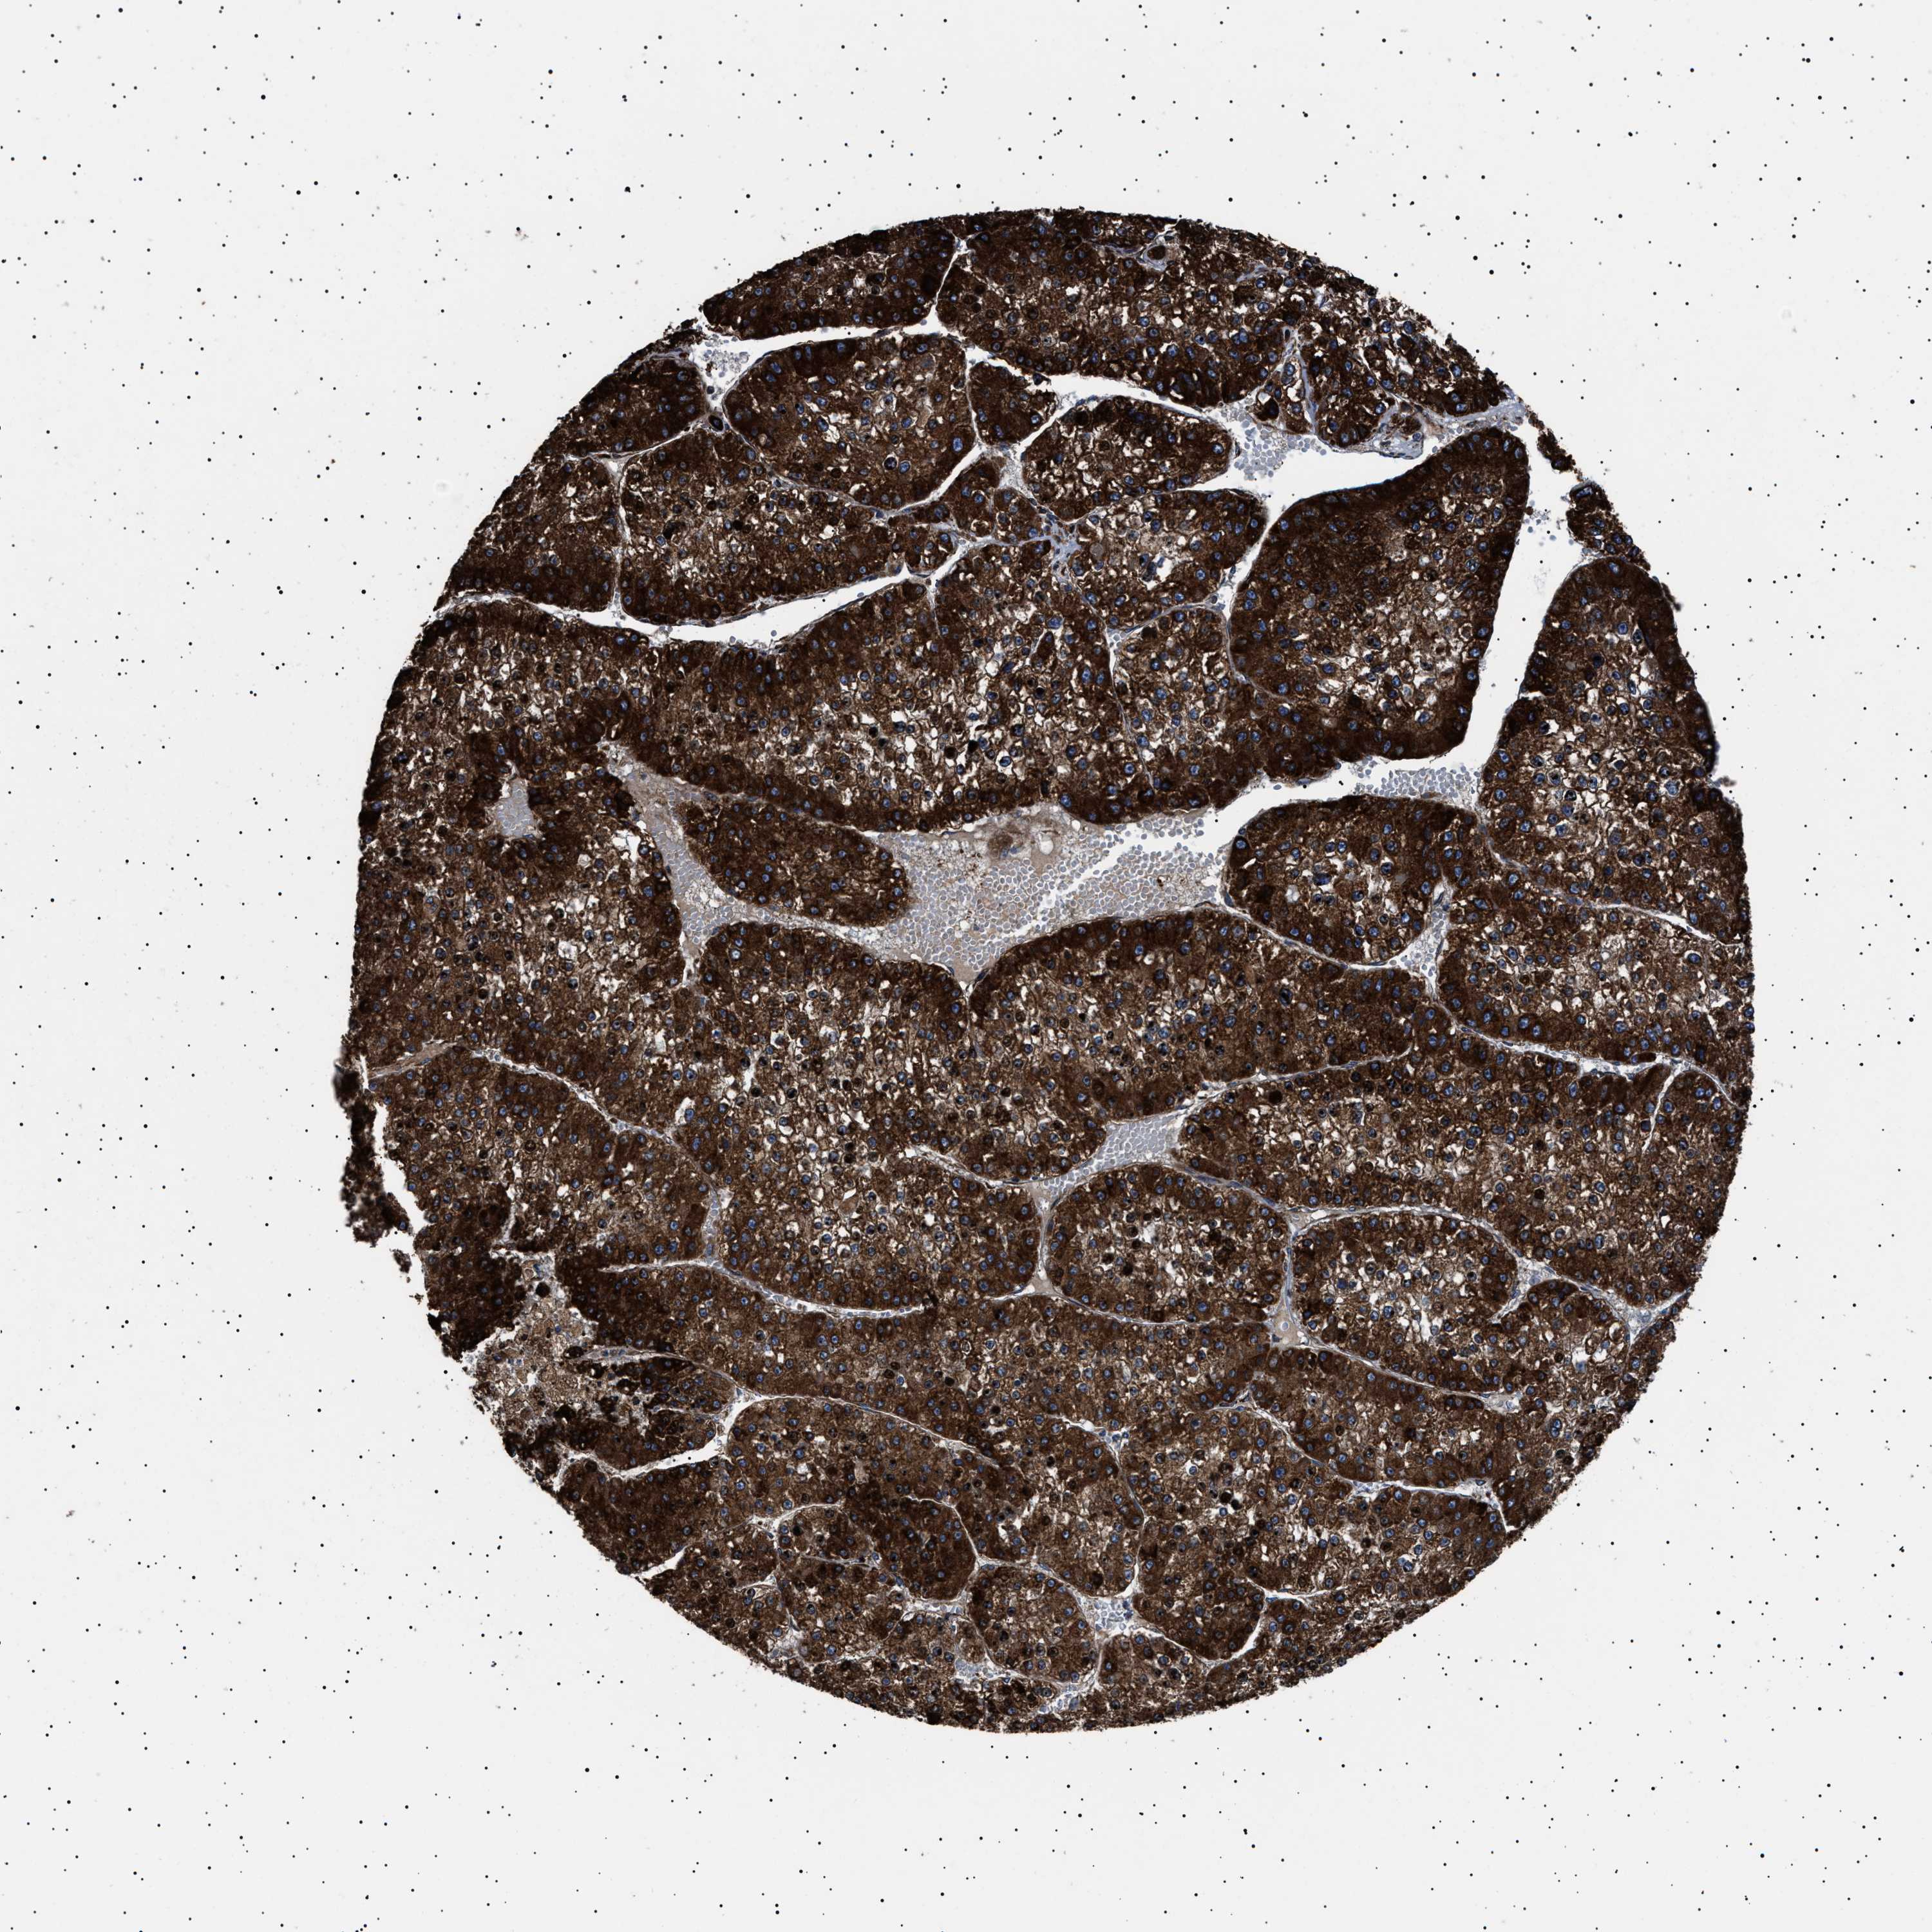

LIVER CANCER - Protein expressioni

A mouse-over function shows sample information and annotation data. Click on an image to view it in a full screen mode. Samples can be filtered based on level of antibody staining by selecting one or several of the following categories: high, medium, low and not detected. The assay and annotation is described here.

Note that samples used for immunohistochemistry by the Human Protein Atlas do not correspond to samples in the TCGA dataset.

Antibody stainingi

Antibody staining in the annotated cell types in the current human tissue is reported as not detected, low, medium, or high, based on conventional immunohistochemistry profiling in selected tissues. This score is based on the combination of the staining intensity and fraction of stained cells.

Each image is clickable and will lead to virtual microscopy that enables deeper exploration of all samples and also displays staining intensity scores, fraction scores and subcellular localization as well as patient and tissue information for each sample.

Antibody HPA001915

Antibody HPA021542

Staining

High

Medium

Low

Not detected

Intensity

Strong

Moderate

Weak

Negative

Quantity

>75%

75%-25%

<25%

None

Location

Nuclear

Cytoplasmic/membranous

Cytoplasmic/membranous,nuclear

Cholangiocarcinoma

Carcinoma, Hepatocellular, NOS